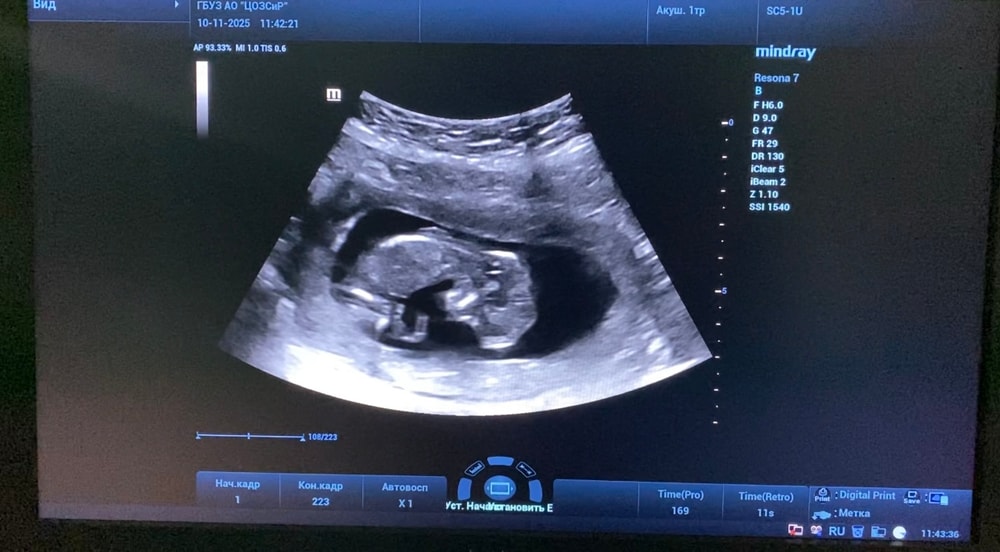

1 скрининг 13+5

Анализы, скринингиНаконец то сходила на 1 скрининг

Малыш развивается хорошо, по крови низкие риски. В целом все хорошо, но есть но.. У пуповины 1 артерия (2 сосуда, вместо 3). Узист успокоила меня, сказала что с малышом все в порядке и это бывает вариантом нормы. Завтра пойду к гинекологу, посмотрим что скажет.

Если тут есть эксперты, делитесь своим мнением какой пол у пупсика :) Попыталась выловить более-менее скриншоты из видео